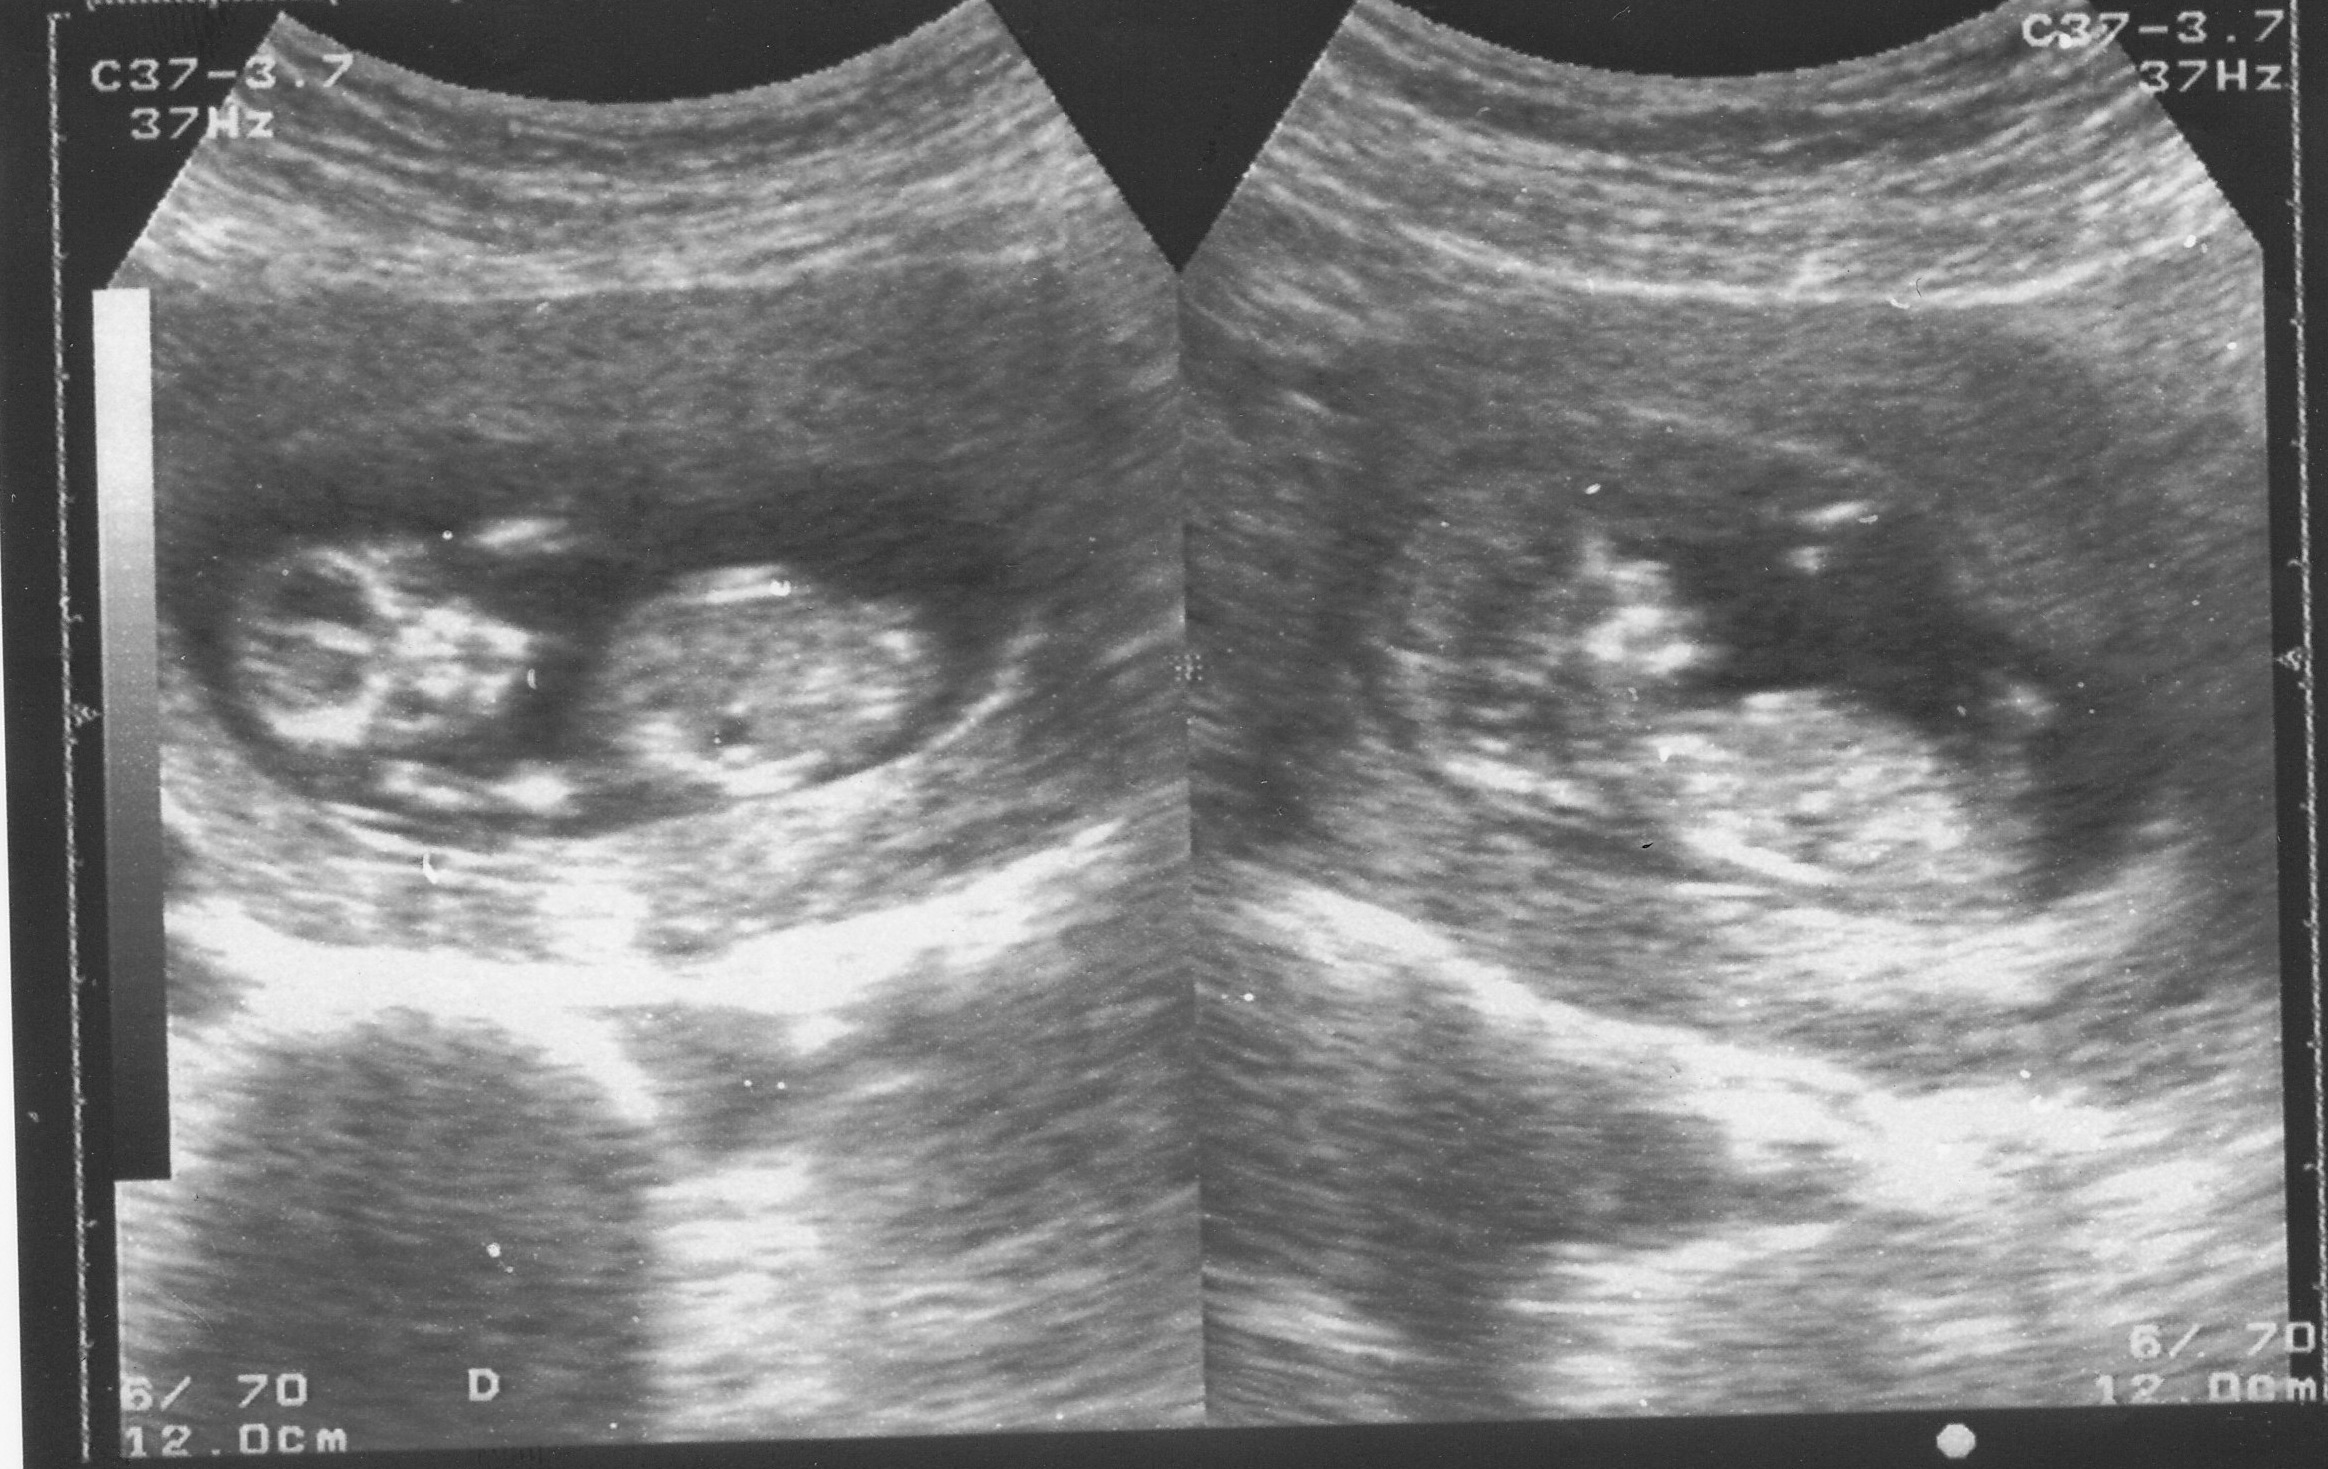

This s the 12th week scan of my second baby...can summone help me in predicting the gender of my baby...Attachment 12495

Zoomed in, thinking maybe, maybe boy on the side shot one. I can't really tell for sure because the pics are a bit grainy. But I am seeing what looks to be nub angled upward. So I file a boy guess.